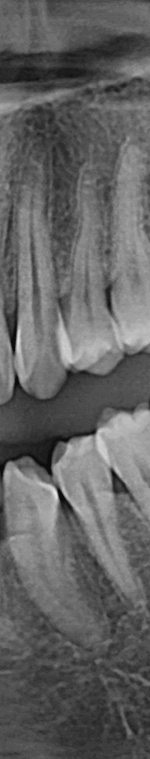

사랑니발치를 하기 위해서는 먼저 파노라마 x선 사진을 통해 발치 시 신경에 영향을 줄 수 있는지 확인하는 과정을 진행했어요. 이 과정을 통해서 충분히 의사와 상담을 한 후 처방전을 발급했어요. 이 때 처방전에는 항생제를 포함하여 발치 후 통증을 대비한 진통제를 처방했어요. 환자에게 충분히 설명한 후에 국소마취를 진행하고 마취가 된 다음에 절개를 최대한 덜 하는 방향으로 수술하여 사랑니를 발치했어요.

턱 뼈와 치아 사이에 공간이 충분하지 않기 때문에 누워서 올라오거나 매복되어 자라는 경우가 많았어요. 반포치과를 찾는 분들의 사랑니의 경우 매복된 경우도 많고 이가 완전히 잇몸 밖으로 나오지 않아서 일반 치과에서는 발치가 어려웠어요. 사랑니발치가 왜 필요한지 가끔 의문을 가지는 분이 계셨어요. 사랑니발치를 왜 해야 하는지 알려드리겠어요. 사랑니는 다른 치아처럼 바르게 나는 경우도 드물게 있긴 하지만 대부분 어금니 쪽으로 기울어져서 올라오거나, 완전히 수평으로 누워서 자라는 경우도 있었어요. 누워서 자라는 치아는 옆의 치아를 밀어 치열이 비뚤어지고 부정교합을 유발했어요.

사랑니가 90도로 누워서 난 경우는 수평 매복, 뼈나 잇몸에 사랑니가 완전히 덮여서 아예 보이지 않는 경우는 완전 매복, 일부분만 잇몸이나 뼈에 덮여있는 경우 부분매복이라고 했어요. 대부분의 환자분이 이런 매복 중에 한 가지에 해당하기 때문에 시술이 매우 어려웠어요. 특히 사랑니 주변으로는 구강과 관련된 중요한 신경 조직이 인접하여 있기 때문에 고난이도 시술이라고 할 수 있었어요.